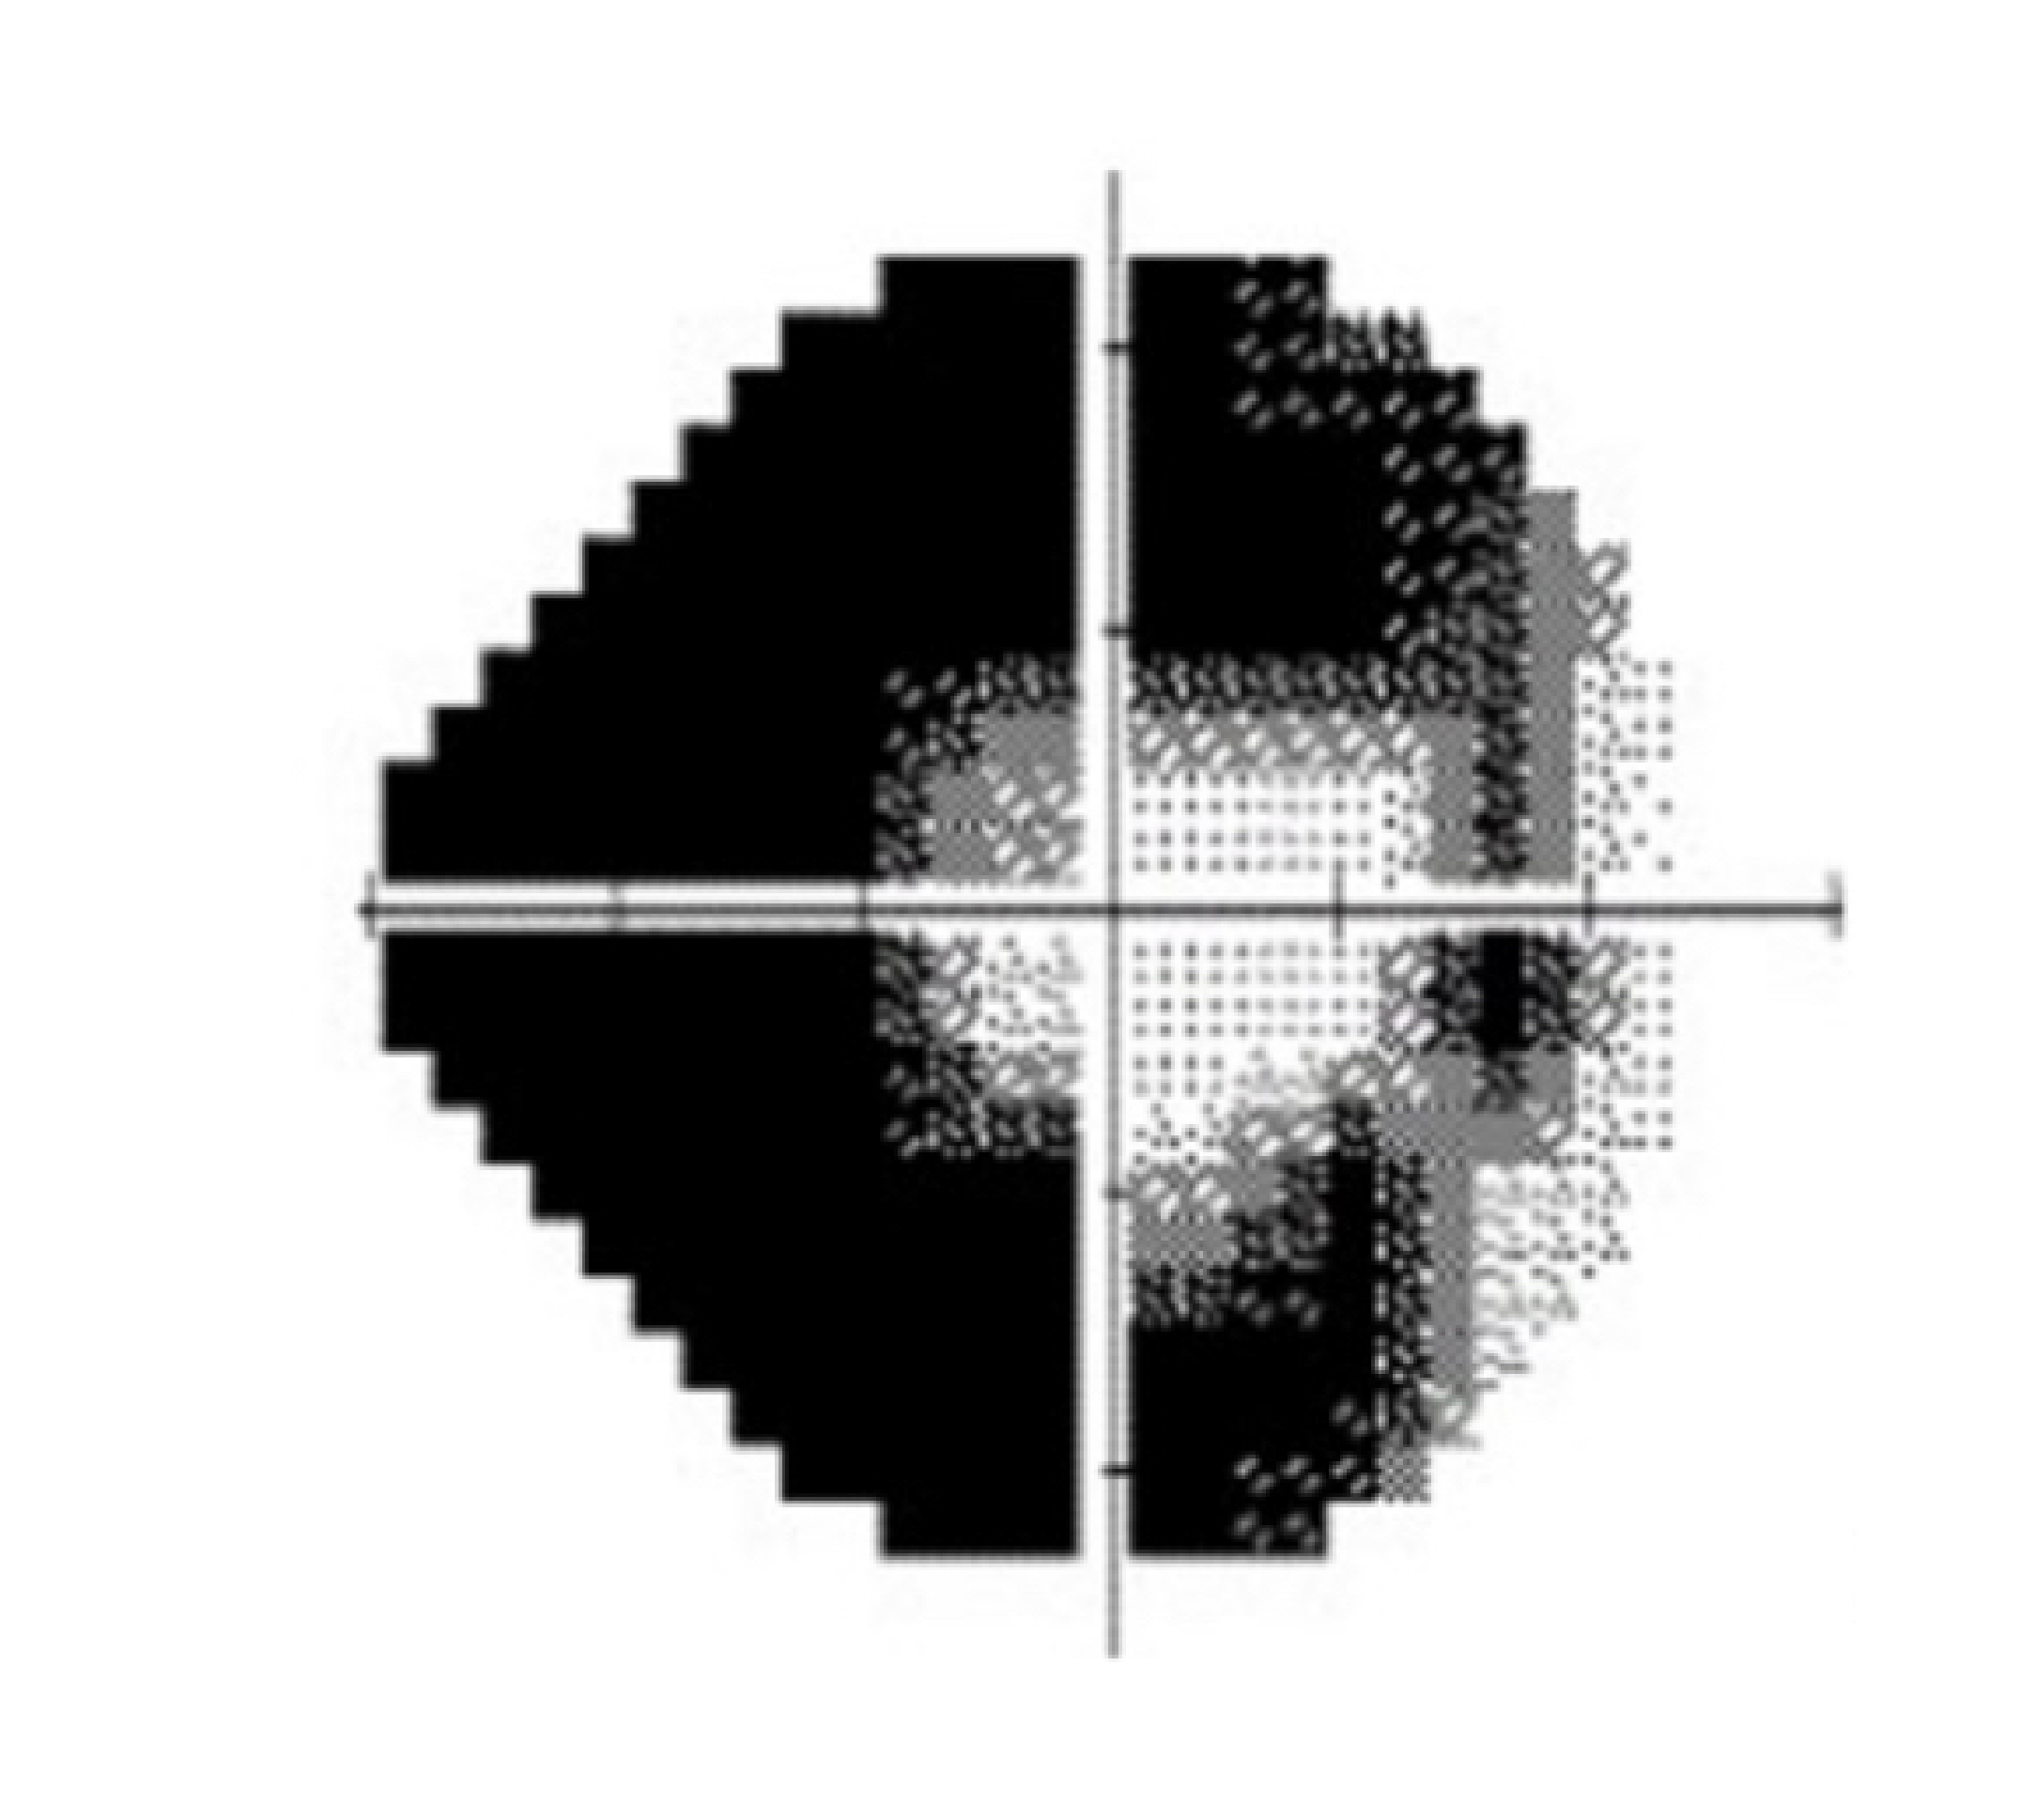

Glaucoma refers to the progressive destruction of vision nerve fibres that transmit signals to the vision processing centre of the brain. These nerve fibres are very sensitive to the pressure and blood supply within the eye. If both the eye pressure and blood supply are poorly regulated, these vital nerve fibres gradually die off, leading to permanent loss of vision.

The brain often fails to recognise that peripheral patches of vision are missing until the damage from glaucoma is significant. Although glaucoma is not curable, and vision already lost cannot be regained, it can be managed adequately to prevent any further vision loss or blindness.

Testing includes Visual filed assessment, Optic nerve fibre digital scans and photographic analysis, as well as eye pressure & structural assessment. If you have glaucoma, treatment can begin immediately to preserve your vision. It is a chronic condition that must be monitored for life.